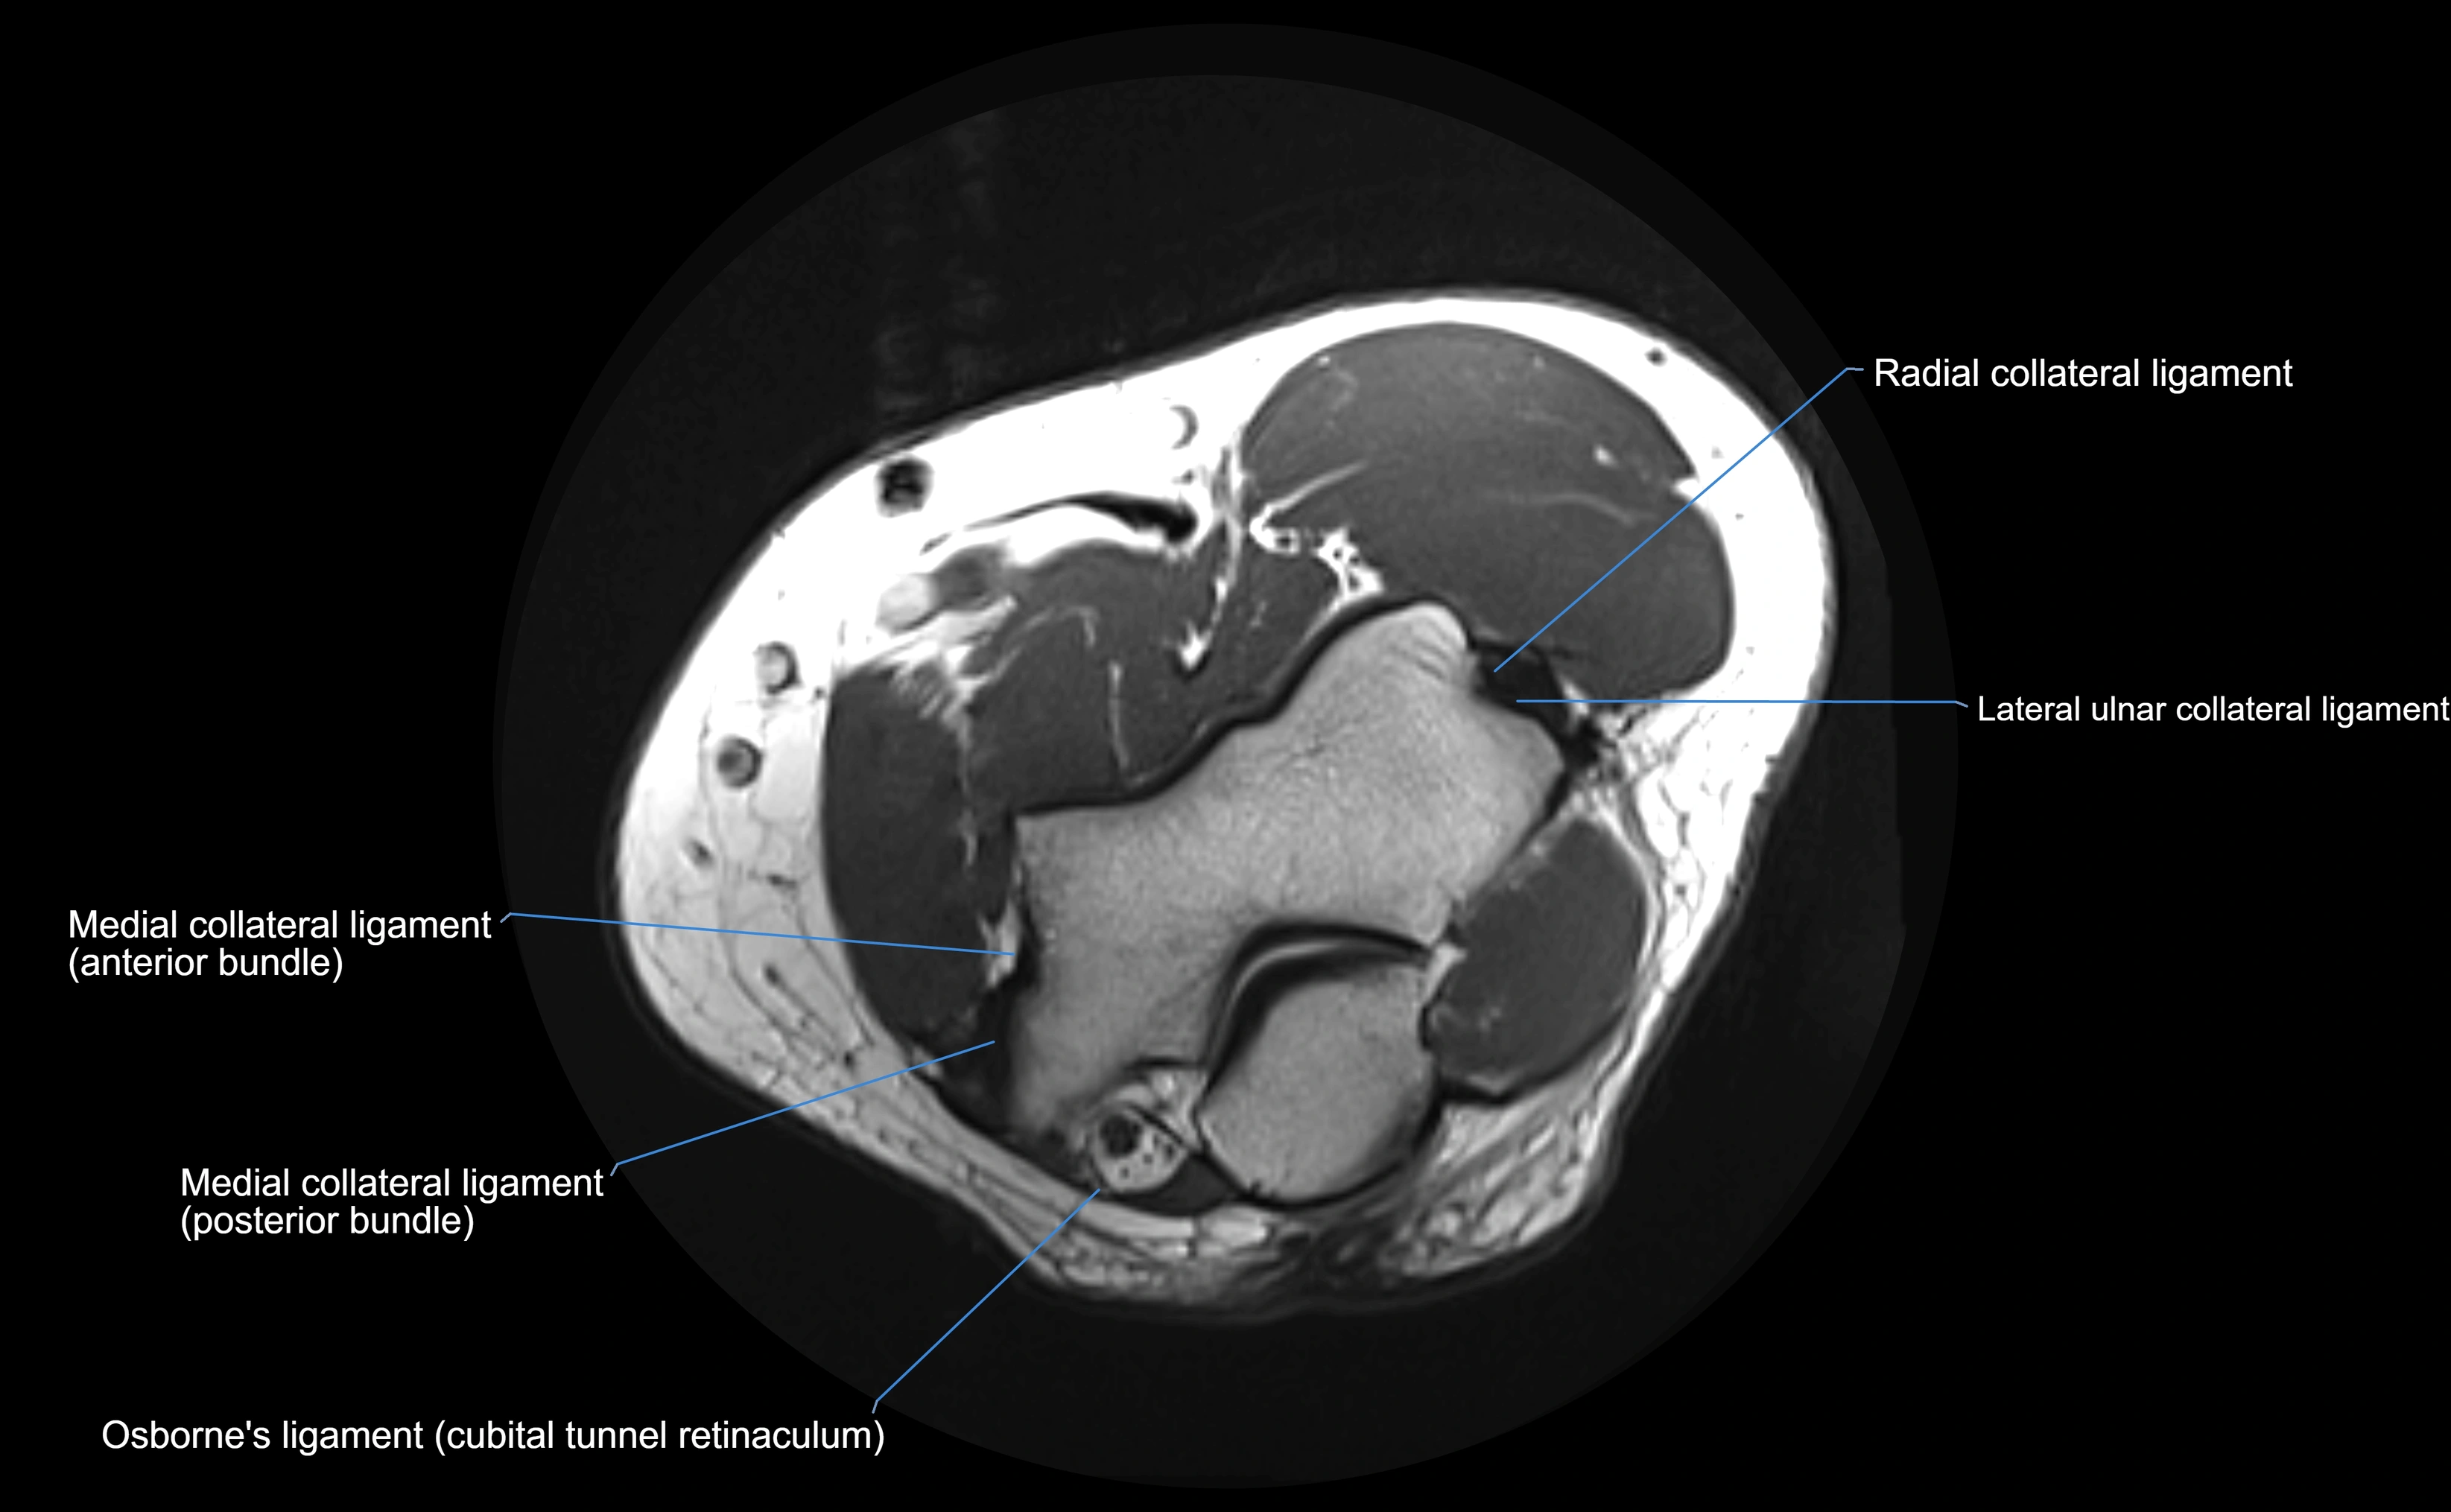

MRI images

image